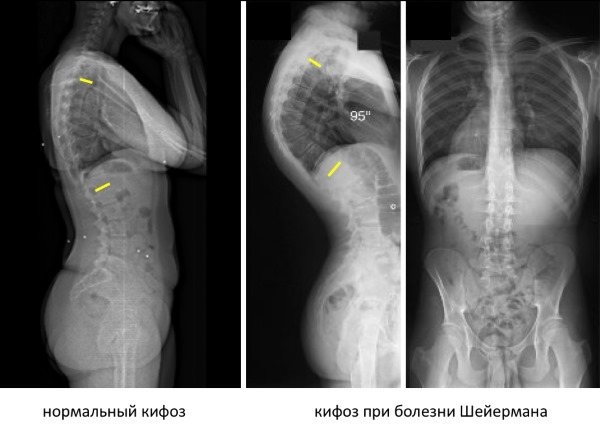

Под кифозом понимают патологическое изменение формы позвоночного столба в передне-заднем направлении. Если угол изгиба не превышает 30°, то речь идет о физиологической выпуклости. Если этот показатель выше, то врачи ставят диагноз «кифоз».

- Рентгеновское исследование. Диагностика заболевания с помощью рентгена проходит по методу Кобба. Она заключается в том, что на снимках в передне-задней проекции проводят линии по верхней границе самого верхнего нейтрального позвонка и по нижней границе самого нижнего. Перпендикулярно им проводят другие линии. На их пересечении измеряют градус угла искривления. Для категории Б и В должен быть угол искривления более 50 градусов.

Обратите внимание на то, как выглядит кифоз на рентгене

- Рентген в прямой и боковой проекции. Оценить степени искривления поможет метод Кобба. Для этого на рентгеновском снимке (боковая проекция) ставят точки в центре позвоночника на вершине изгиба и позвонках по краям. Потом их соединяют линиями в треугольник и продлевают боковые стороны. Полученный угол – это показатель степени искривления.